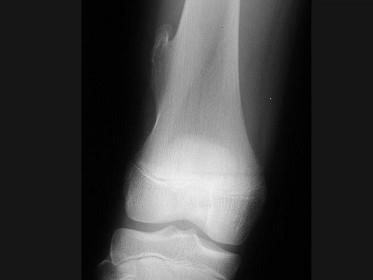

问题 男,13岁,运动后膝痛,请结合影像图像,选择最可能的诊断 ( )

选项 A、成骨细胞瘤 B、骨样骨瘤 C、动脉瘤样骨囊肿 D、骨软骨瘤 E、正常影像

答案 D